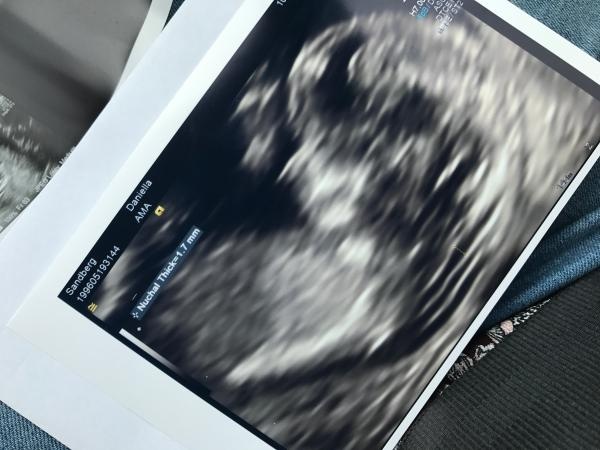

Skulle vara jättekul om någon ville gissa! Vecka 12+5 på dessa bilder! är i vecka 20 nu och får förhoppningsvis reda på svaret nästa vecka!